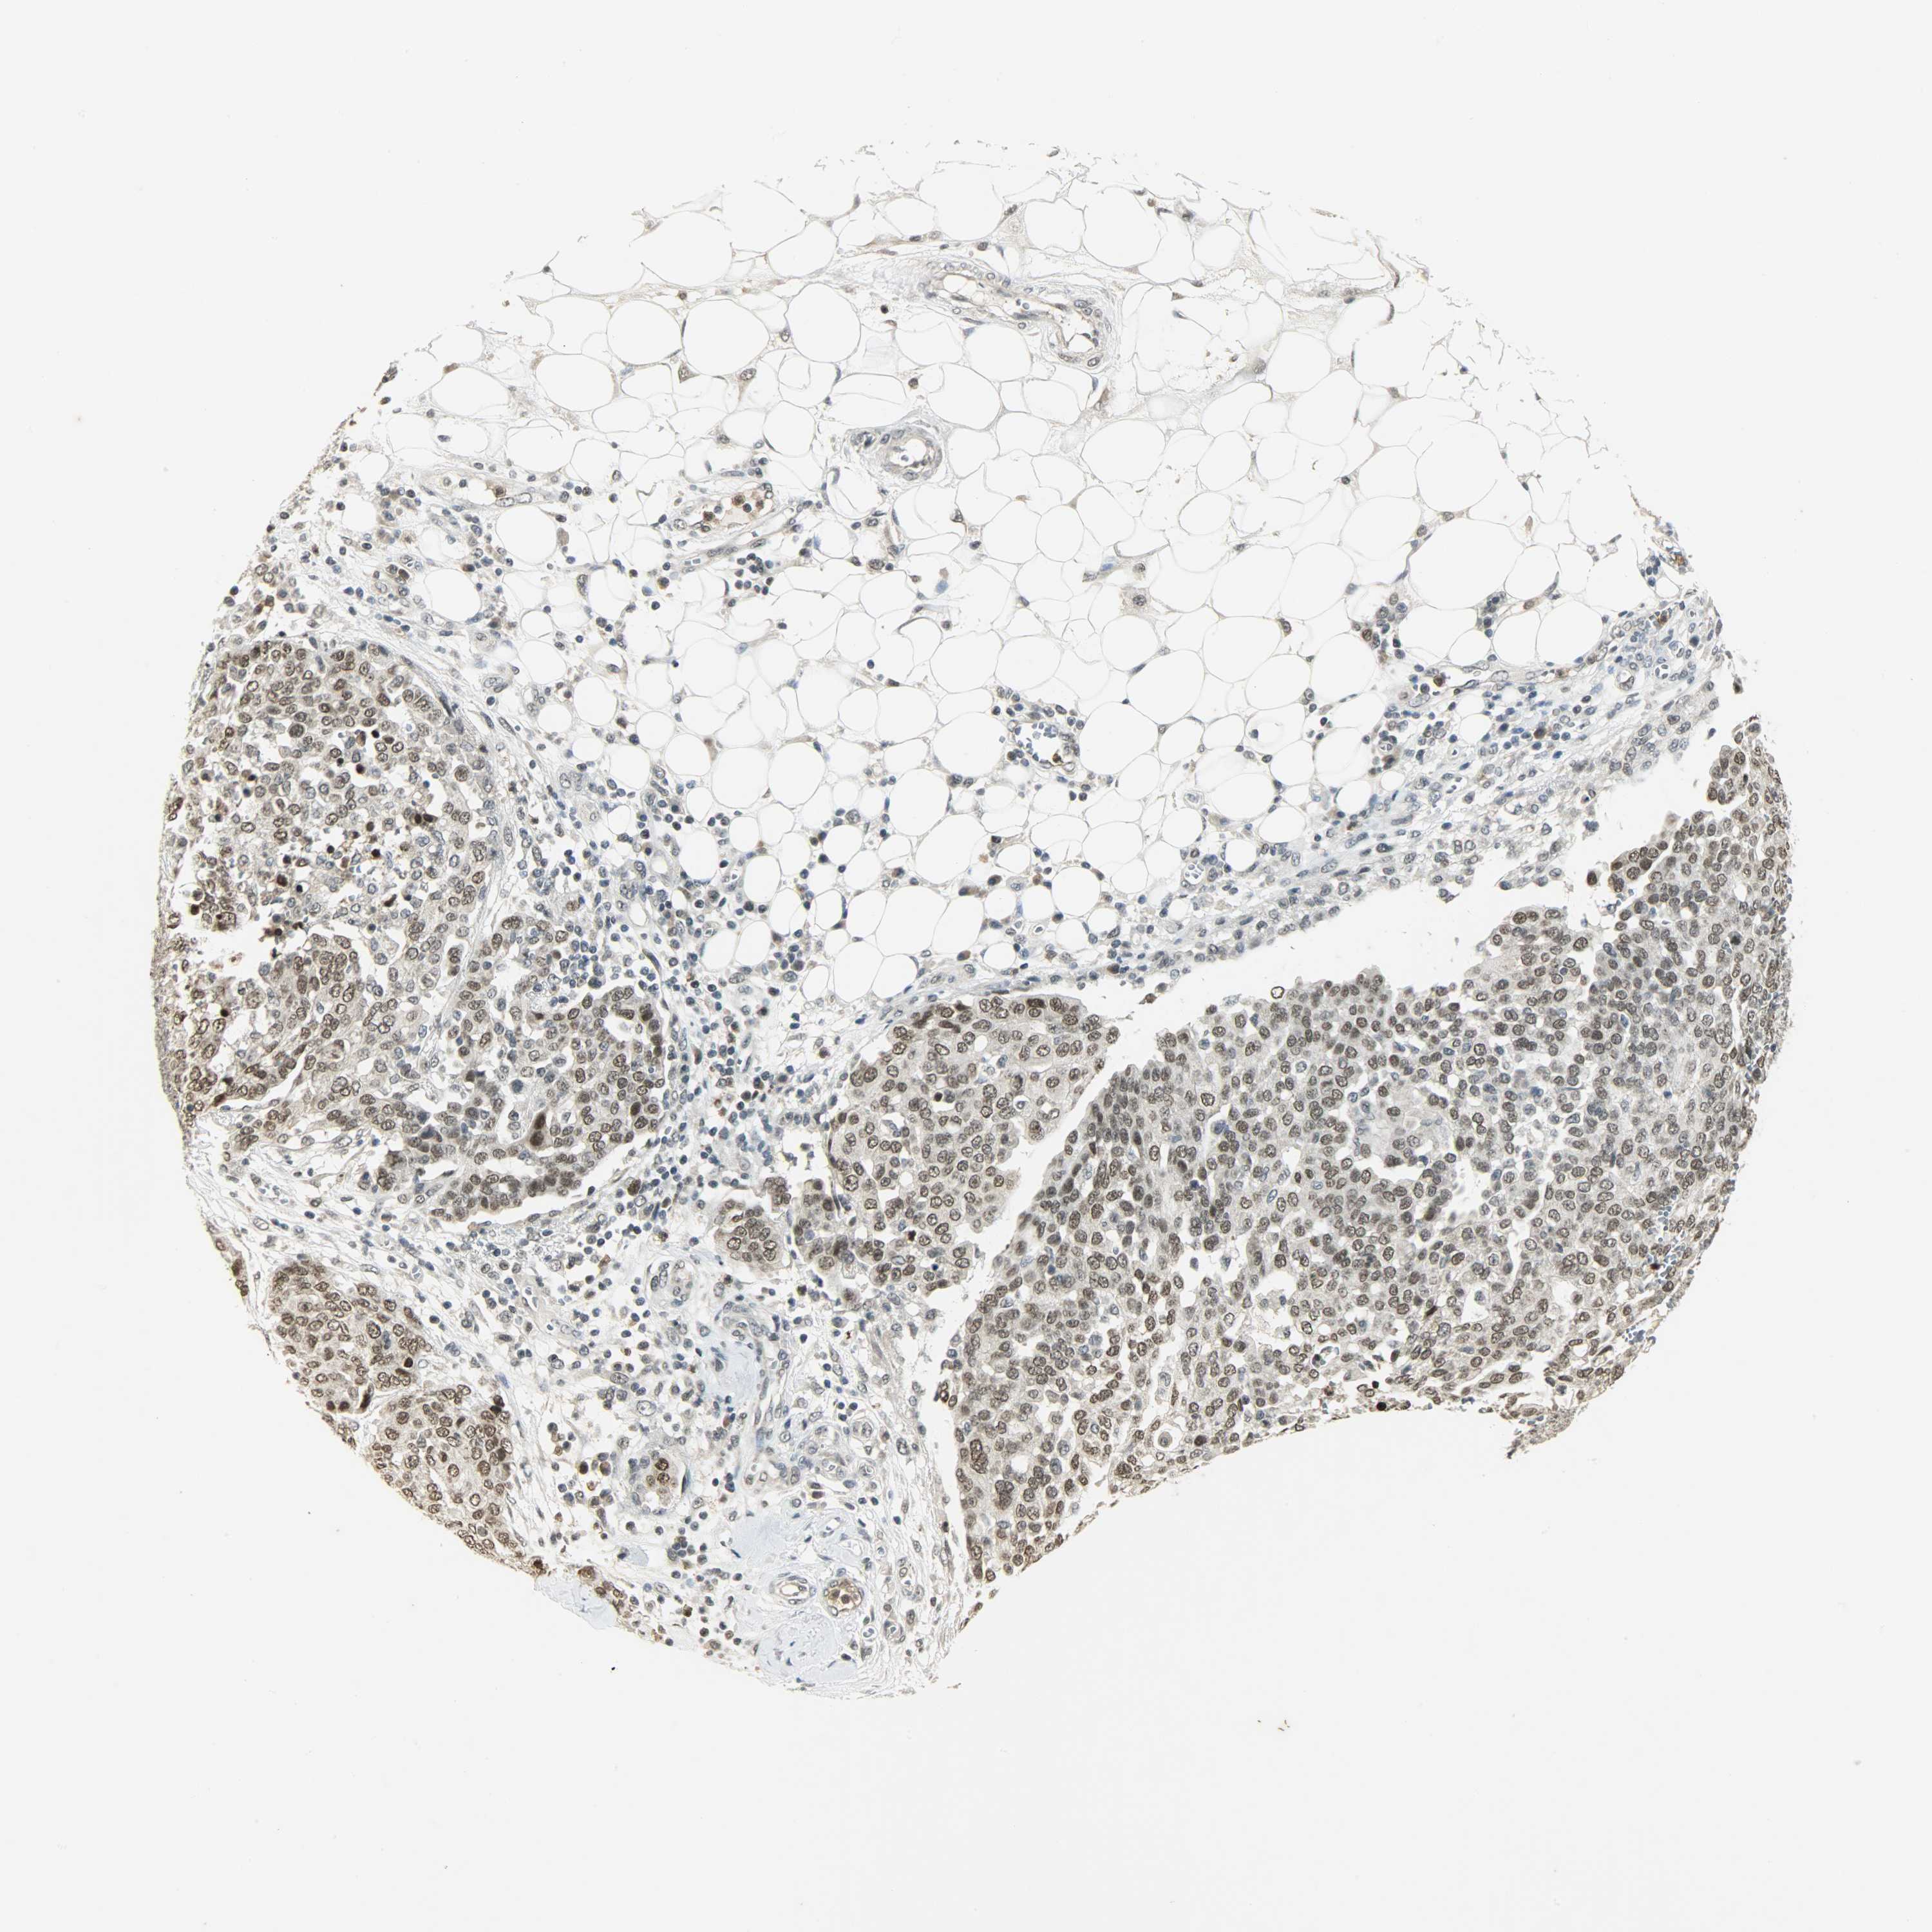

OVARIAN CANCER - Protein expressioni

A mouse-over function shows sample information and annotation data. Click on an image to view it in a full screen mode. Samples can be filtered based on level of antibody staining by selecting one or several of the following categories: high, medium, low and not detected. The assay and annotation is described here.

Note that samples used for immunohistochemistry by the Human Protein Atlas do not correspond to samples in the TCGA dataset.

Antibody stainingi

Antibody staining in the annotated cell types in the current human tissue is reported as not detected, low, medium, or high, based on conventional immunohistochemistry profiling in selected tissues. This score is based on the combination of the staining intensity and fraction of stained cells.

Each image is clickable and will lead to virtual microscopy that enables deeper exploration of all samples and also displays staining intensity scores, fraction scores and subcellular localization as well as patient and tissue information for each sample.

Antibody HPA008751

Antibody CAB005227

Cystadenocarcinoma, serous, NOS

Carcinoma, endometroid